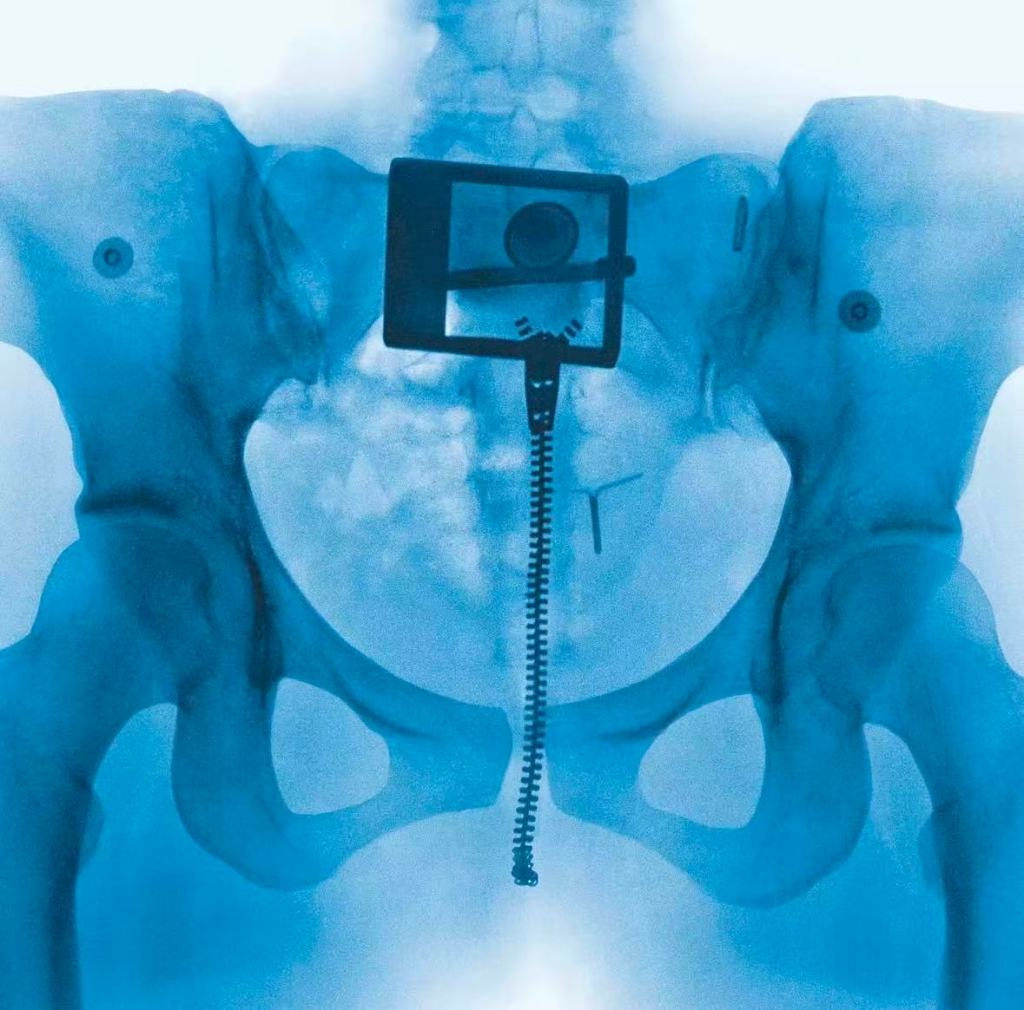

Lorde — 「VIRGIN」

With the release of her new album Virgin, Lorde returns to the stage with the Ultrasound Tour—a performance that feels raw, intimate, and completely unrestrained. Stripped of the elaborate theatrics of her earlier eras, this show focuses instead on emotional honesty and physical presence.

it’s a living, breathing portrait of what it means to keep searching for oneself in front of thousands of people.

2